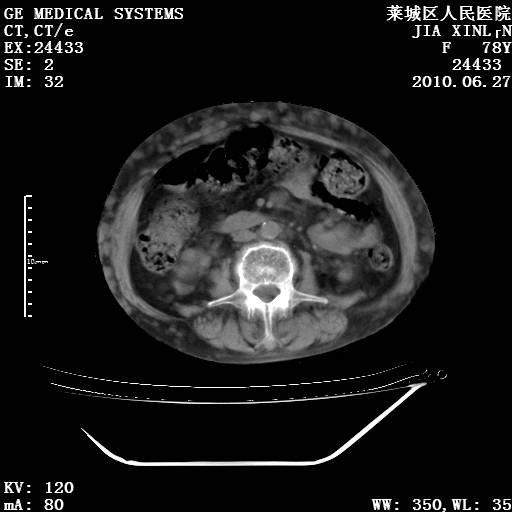

以下是引用胡宇在2010-7-2 19:11:00的发言:[br]神经纤维瘤的特点为:肿块呈多发性、数目不定,少的几个,多的可成百上千难以计数。小的如米粒,大的似拳头,甚至可达十数公斤以上。可松弛地悬挂于皮表,皱褶及松弛可致畸形明显。神经纤维瘤沿神经干的走向生长时呈念珠状,或蚯蚓块状形结节。此外神经纤维瘤皮肤可出现咖啡斑,大小不一,形如雀斑小点状,或大片状,分布与神经纤维瘤肿块的分布无关。肿瘤数目不多的患者,皮肤色素咖啡斑状沉着是纤维神经瘤的重要诊断之一。 本病多发于躯干,有时出现于四肢及面部,患者常合并许多疾病应予重视加以区别。 [br] [br] [br] [br]lyb999说 [br]